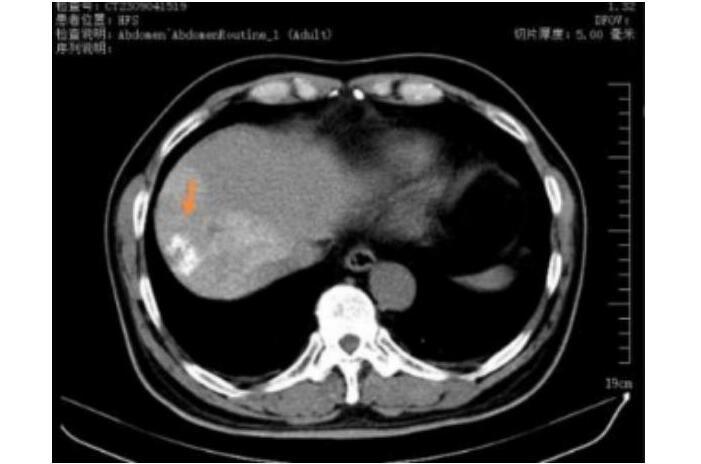

三个月复查图像 肿瘤完全灭活